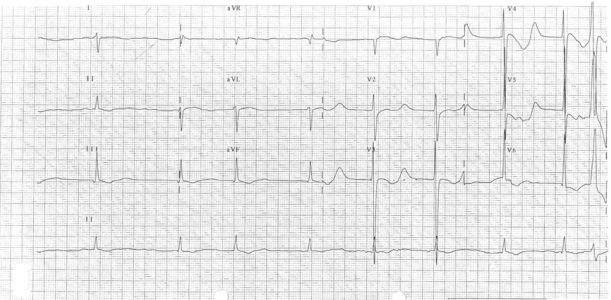

33 一位 28 歲女性最近半年來臉頰部有紅斑(如附圖)及手指、手腕和肩膀有偶發性疼痛。曾經被醫師懷疑為紅斑性狼瘡。請問下列那些檢查對疾病的診斷最有幫助?

① skin biopsy ② anti-nuclear antibodies ③serum complements C3 and C4 level ④rheumatoid factors ⑤complete blood routine ⑥ anti-dsDNA antibodies ⑦ anti-SS-A/anti-SS-B ⑧ serum electrophoresis ⑨ LE test(A)①④⑧(B)③⑦⑨(C)②③⑥(D)④⑤⑦